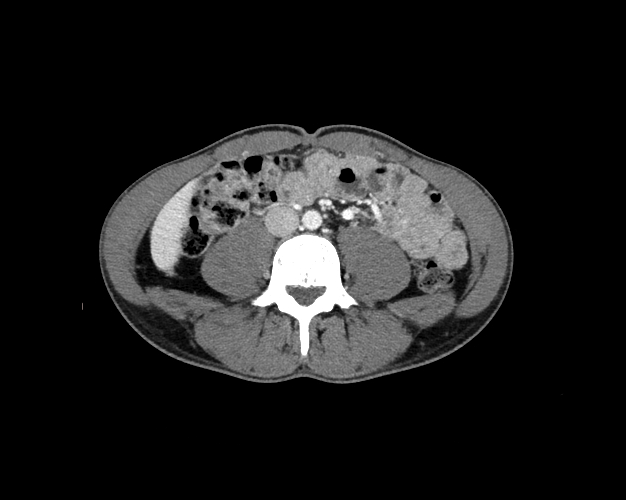

Body

Covers abdominal CT anatomy.